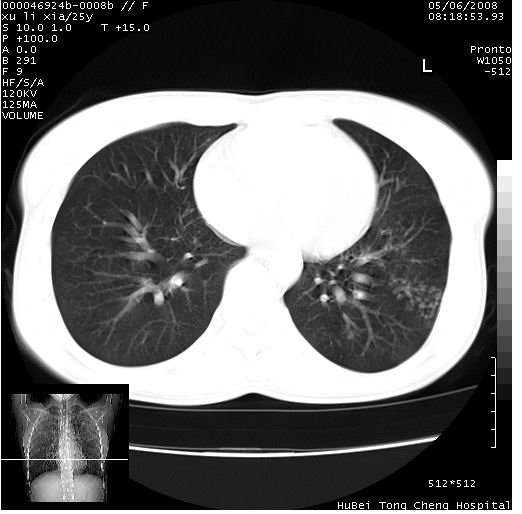

患者 女,25岁。因“左侧卵巢肿瘤”术前胸片偶然发现两肺病变。平素无明显不适,无呼吸系统症状及体征,无传染病史。

cr x线胸片提示:两肺感染性病变(结核可能性大)。

胸部ct轴位平扫(层厚10mm,螺距1.5,重建间隔10mm),图像如下:

(注:上级医院会诊胸部ct片——考虑为肺部真菌感染。)

病灶呈地图样分布于肺外围,与正常组织分界清晰+弥漫性磨玻璃影中见小叶间隔增厚呈碎石路样表现+年轻女性,无明显临床症状=肺泡蛋白沉积症?

双肺病灶以渗出影搀杂斑点状阴影为主,部分阴影融合成团片,并沿纹理明显见播散灶。支持楼主:两肺感染性病变(结核可能性大)!

平行于间质走行微结节影;拌钙化灶;分布通气好的肺野